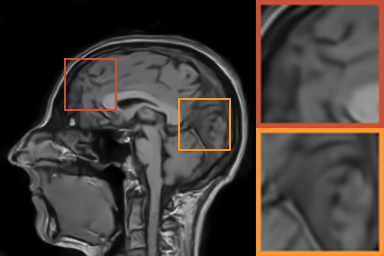

As shows in Fig. 1, at the first several iterations, the loss of is slightly larger than that of . Because the input is corrupted with severe artifacts, thus the role of data-driven module is significant at the first several steps. But as process goes on, repeated denoising operation in turn causes over-smoothing. While module can make up for it by incorporating model based knowledge. Though can improve the performance, it cannot ideally converge to a desired solution. The solid line indicates the superiority of Ours over other choices in both convergence rate and reconstruction accuracy. The execution time of , , and Ours is 4.4762s, 3.3240s, 6.2760s and 2.5225s, respectively. As expect, the proposed method provides a much faster reconstruction process. Thus we can verify that our framework has higher efficiency both in terms of theoretical convergence and practical execution time. The visualized results in Fig. 2 also verify that Ours has better performance than others.

First, we test on 25 T1-weighted MRI data using three different undersampling patterns with a fixed 10% sampling rate. Fig. 3 shows the quantitative results (PSNR). Our method performances best for all three cases and has stronger stability compared with the second best method on variance. As for the effect of sampling ratios variation, we use radial mask under 10%, 30% and 50% sampling rates with evaluation of RLNE and MSE. Fig. 4 shows that our method has the lowest reconstruction error for all sampling rates. For more intuitive comparison, we illustrate the reconstruction error in term of pixels in Fig. 5. We also offer the qualitative comparison in Fig. 6. Visualized results demonstrate our method has better performance in both artifacts removing and details restoration. Time consuming is also considered. We compare our method with others on the 25 T1-weighted data using Radial mask with 10% and 50% sampling rate. Notice that ADMM-Net and ours are tested on GPU for the incorporation of deep architecture. Tab. 1 shows that our method provides an efficient reconstruction process and comes to the fastest method among the state-of-the-art competitors.

To demonstrate the robustness of our approach, we first apply it on various MRI data including the chest, cardiac and renal (?). In Tab. 2, Our proposed framework gives the highest PSNR for all of the tree types of MR images. Fig. 7 visualizes the corresponding results for chest data. we can see that our approach prevails over others in detail restoration at the junction of blood vessels as well as noise removal in the background. Actually, our method has a stronger ability to handle slight noise because of the subprocess of learning based optimization with deep prior. To demonstrate that, we add Rician noise at level of 20 to 25 T1-weighted MRI and 25 T2-weighted MRI to generate the noisy data. As what is shown in Fig. 8, our method over leads all the competitors by a large margin when the input is corrupted with Rician noise.